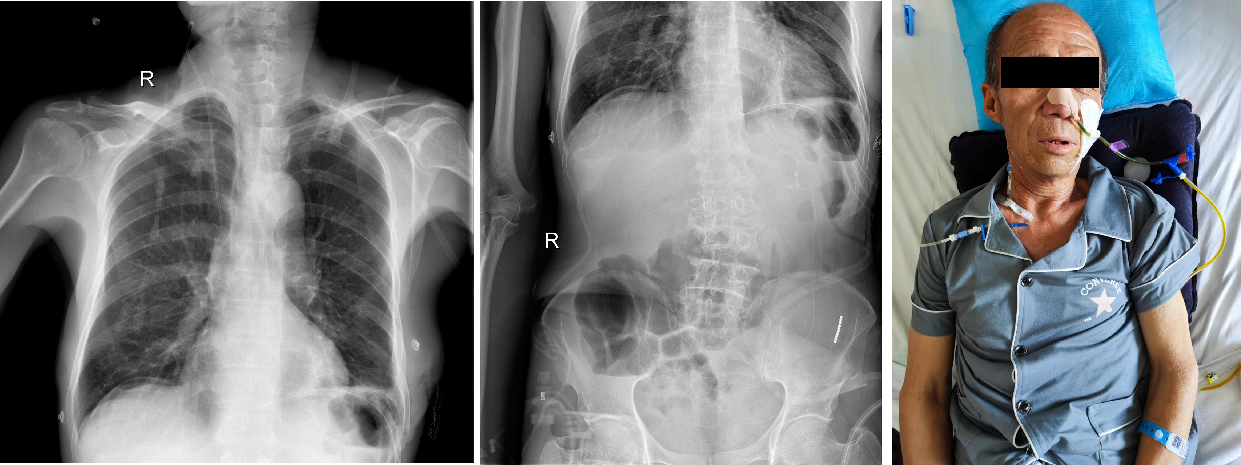

患者因进食梗噎 1 月余就诊于当地医院,行胃镜检查发现食管胃结合部粘膜弥漫性病变。由于病变时间较长,患者迫切地想要获得症状改善,转入我院胸外科。来院后复查电子胃镜示:腹段食管、贲门、胃底、胃体粘膜弥漫性粘膜粗糙、增厚、僵硬,局部粘膜中断。胃镜病理示:低分化癌。消化道钡透示:食管远端、贲门结构不清,胃底、胃体僵硬,管腔狭窄,考虑恶性肿瘤浸润。超声内镜及胸腹部增强 CT 未提示肿瘤侵及临近器官及远处转移。

8 月 1 日,李少民教授带领马跃峰副主任医师、马震川主治医师和郭询医师,首先经左侧第 7 肋间进胸,探查、确认胸段食管未受累及,再切开膈肌探查腹腔,见肿瘤累及腹段食管、贲门、胃底及近端胃体,胃近端大部呈皮革样改变,且与脾门关系密切,为确保将肿瘤完整切除,决定将远端食管-全胃切除,并切除脾脏、清扫淋巴结,采用空肠代食管进行空肠-食管 Roux-en-Y 吻合。术中在保证血供良好前提下游离足够长度的空肠管,距屈指韧带约 30 cm 处离断空肠,将远端空肠的经横结肠系膜上提至胸腔与食管行端-侧吻合,在腹腔内行空肠-空肠侧侧吻合。手术顺利,患者术后生命体征平稳,术后经禁食、静脉营养过渡至肠内营养。